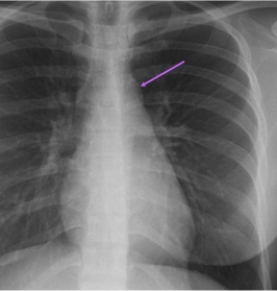

In this AP projection the arrow indicates: